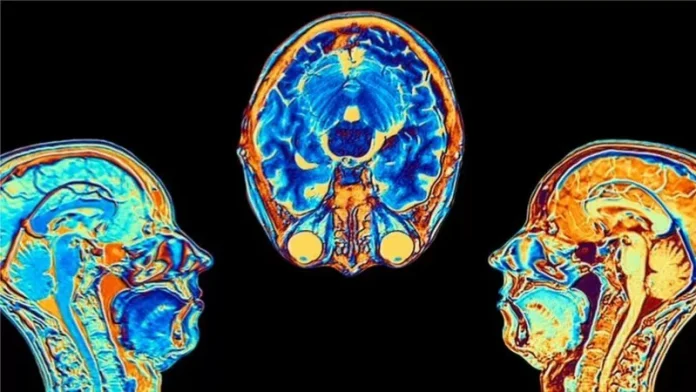

El proyecto UK Biobank ha seguido la salud de 500.000 personas durante aproximadamente 15 años y tiene una base de datos de escaneos registrados antes de la pandemia. Esto brindó una oportunidad única para estudiar el impacto del virus en la salud a largo plazo.

Los investigadores reescanearon a:

- 401 participantes, 4 meses y medio en promedio después de su infección. El 96% con covid leve.

- 384 participantes que no tuvieron covid

Encontraron que:

- El tamaño general del cerebro en los participantes infectados se había reducido entre un 0,2 y un 2%

- Hubo pérdidas de materia gris en las áreas olfativas, vinculadas al olfato, y en regiones vinculadas a la memoria.

- Aquellos que se habían recuperado recientemente de covid tenían un poco más de dificultad para realizar tareas mentales complejas.

FUENTE DE LA IMAGEN,UK BIOBANK